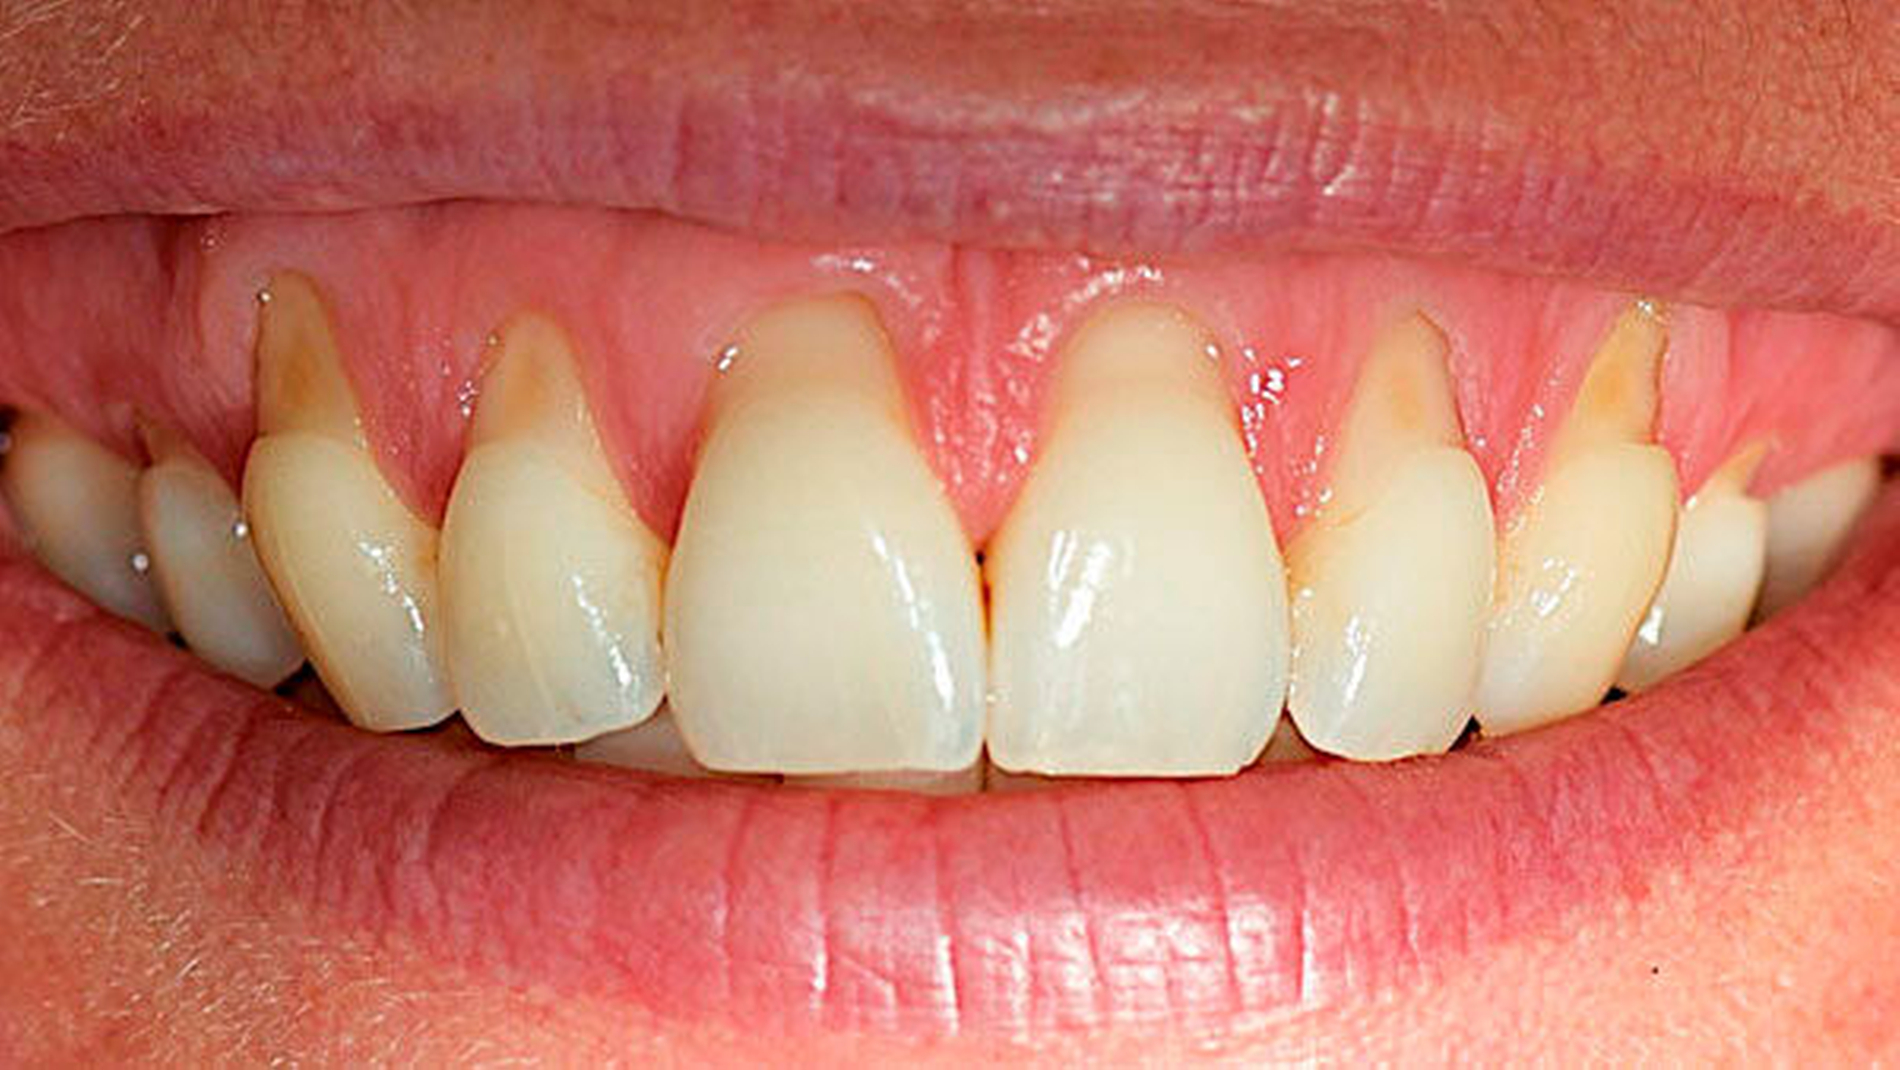

Mukogingivale Zustände

Die Bedeutung des Gingiva-Phänotyps – einschließlich der Gingivadicke und -breite – wird jetzt anerkannt und eine neue Klassifikation für gingivale Rezessionen ist eingeführt worden. Dabei werden klinische Parameter wie der gingivale Phänotyp, der interproximale Attachmentverlust und die Charakteristika der freiliegenden Wurzeloberfläche kombiniert.

Mukogingivale Zustände werden nach gingivalem Phänotyp, interproximalem Attachmentverlust und den Charakteristika der exponierten Wurzeloberfläche klassifiziert.